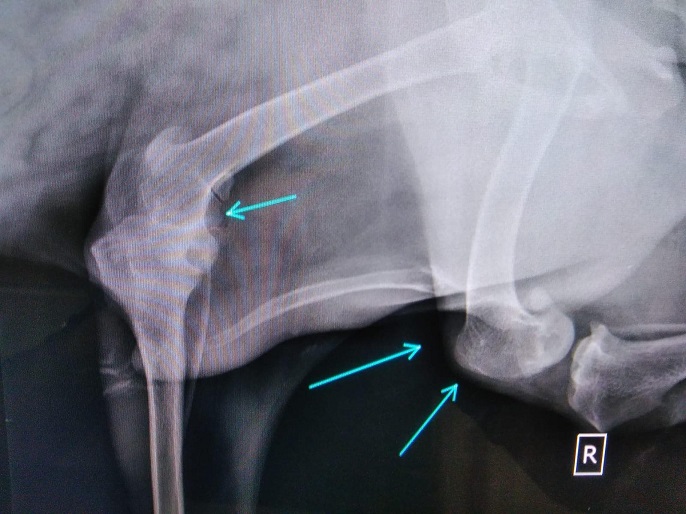

TORIN wurde von Aniela an einer Brücke gefunden, festgebunden mit einem kurzen Stück Kordel. Der super freundliche Kerl war aber quasi nicht im Stande, sich zu bewegen. Beide Hinterläufe konnten nicht richtig benutzt werden, die Knie schienen völlig lädiert zu sein. Schnell war klar, ein Hund wie TORIN (groß, riesen Handicap) wird wenig Chancen haben und kann vor Ort in Rumänien aber auch nicht ausreichend versorgt werden. Der Eulenhof am Niederrhein e.V. hat auch ihn als Gnadenplatzhund aufgenommen und dank seiner tollen Paten geht es nun stetig aufwärts. Neben einer guten Schmerztherapie bekommt TORIN regelmäßige Physiotherapie und kann sich auf dem großen Gelände des Eulehhofs frei bewegen und seine Muskulatur wieder gut aufbauen. Zusätzlich bekommt er sehr viele Zusatzpräparate. All das zusammen hat TORINS Bewegungsablauf massiv verbessert und er kann nun sogar mit anderen Hunden spielen. Er hat wirklich deutlich an Lebensqualität gewonnen und wir freuen uns so sehr, dass ein Notfall wie er diese Chance erhalten hat.